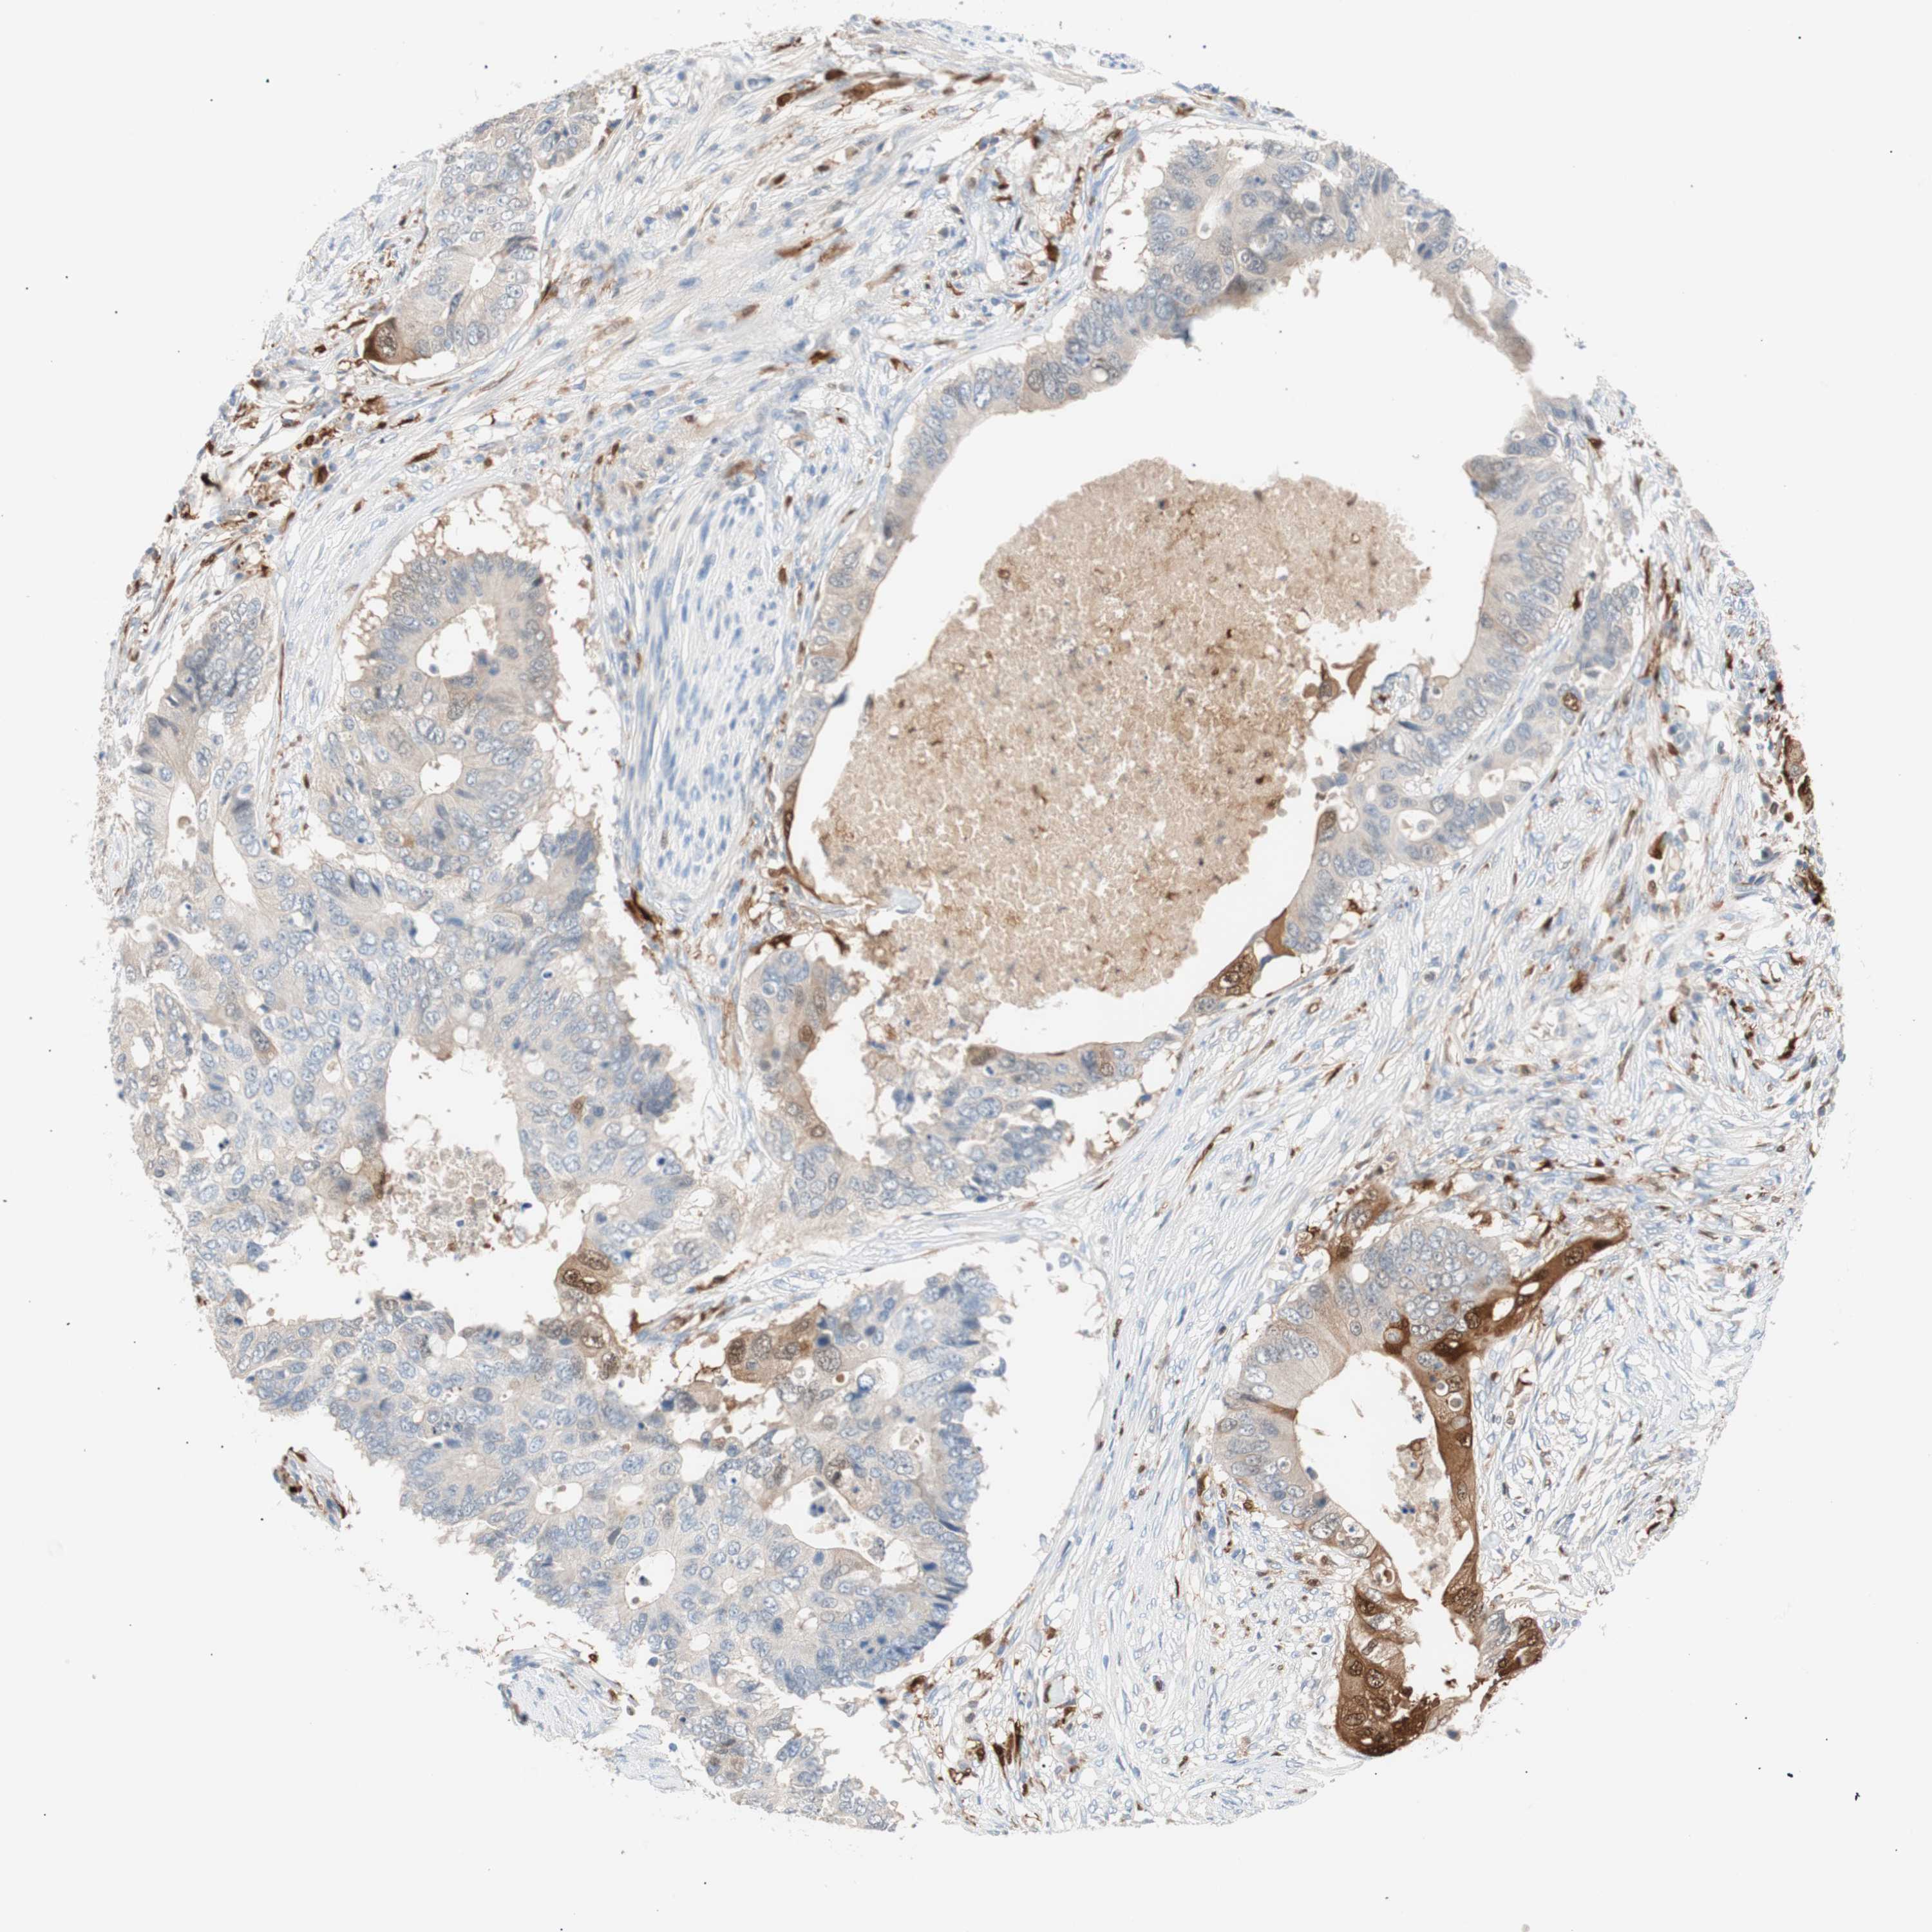

Colorectal cancer

Rectum adenocarcinoma